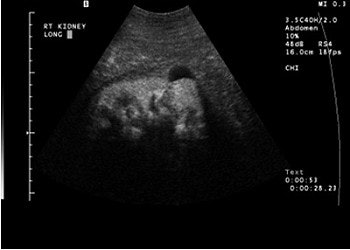

A complex cystic mass with a solid portion slightly higher in echogenicity in the cystic component, pre-contrast (above) and post-contrast administration (below). The echogenic component is markedly enhanced on contrast and is a cystic renal carcinoma. Images courtesy of Dr. Richard Barr, Ph.D.

![]() |